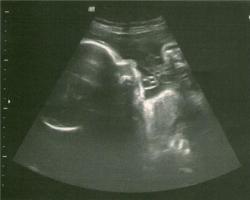

Et il parait même qu'il les fait,

bien avant de naître !!!!

Incroyable, non ?